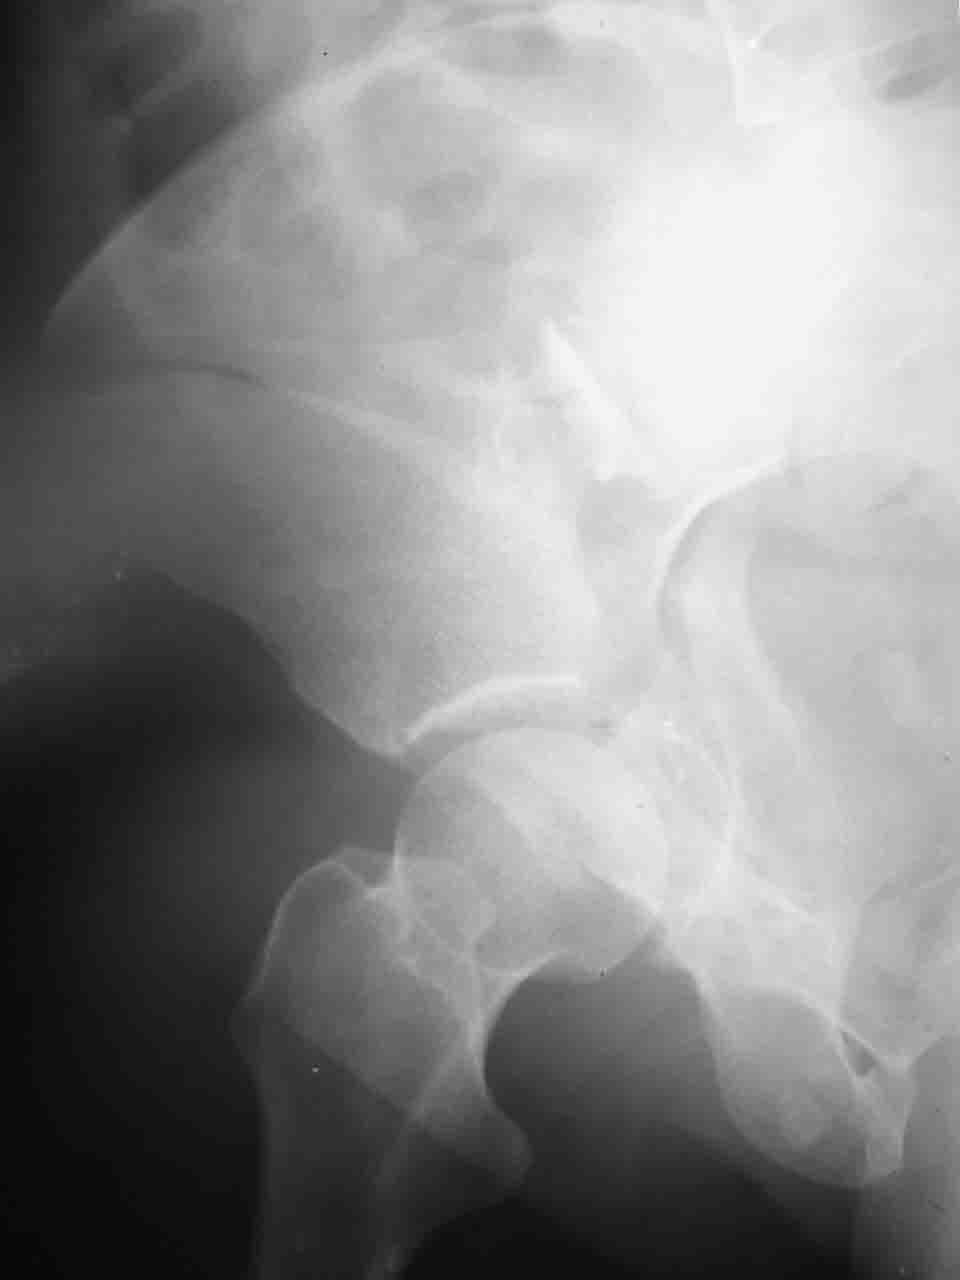

Re: Перелом вертлужной впадины

Смирнов Алексей 09 Ноябрь 2004, 01:17

Снимки и схема